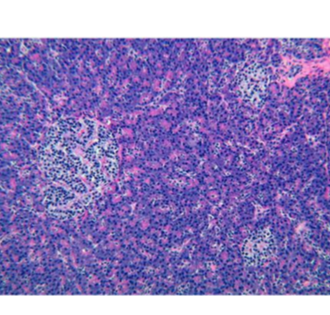

pancreas

islets of langerhan